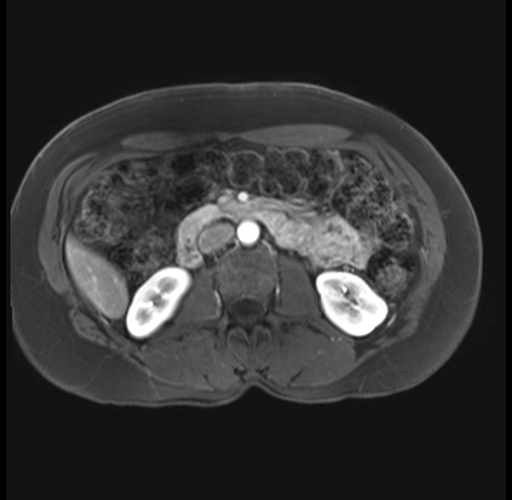

Imaging Analysis

Look through the patient's CT scan to identify any areas of concern for the necessary procedure.

Based on your CT findings, which issue(s) are present and would give reason for "planned slowing down moment(s)" in this case?

Considering a standard distal pancreatectomy procedure, what step(s) of the operation would you do differently in this case?